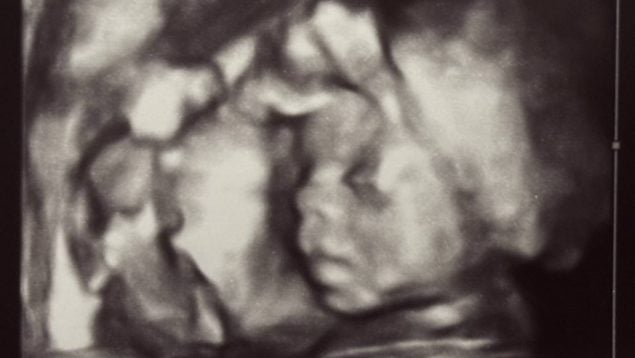

Durante el embarazo y la lactancia, la alimentación de la madre influye directamente en la salud, el crecimiento y el desarrollo del bebé. Mantener una dieta equilibrada, variada y segura ayuda a prevenir complicaciones gestacionales y déficits nutricionales, además de favorecer una recuperación posparto adecuada. Esta etapa requiere una atención nutricional especifica y un acompañamiento médico completo que aporte tranquilidad y respaldo a las familias.